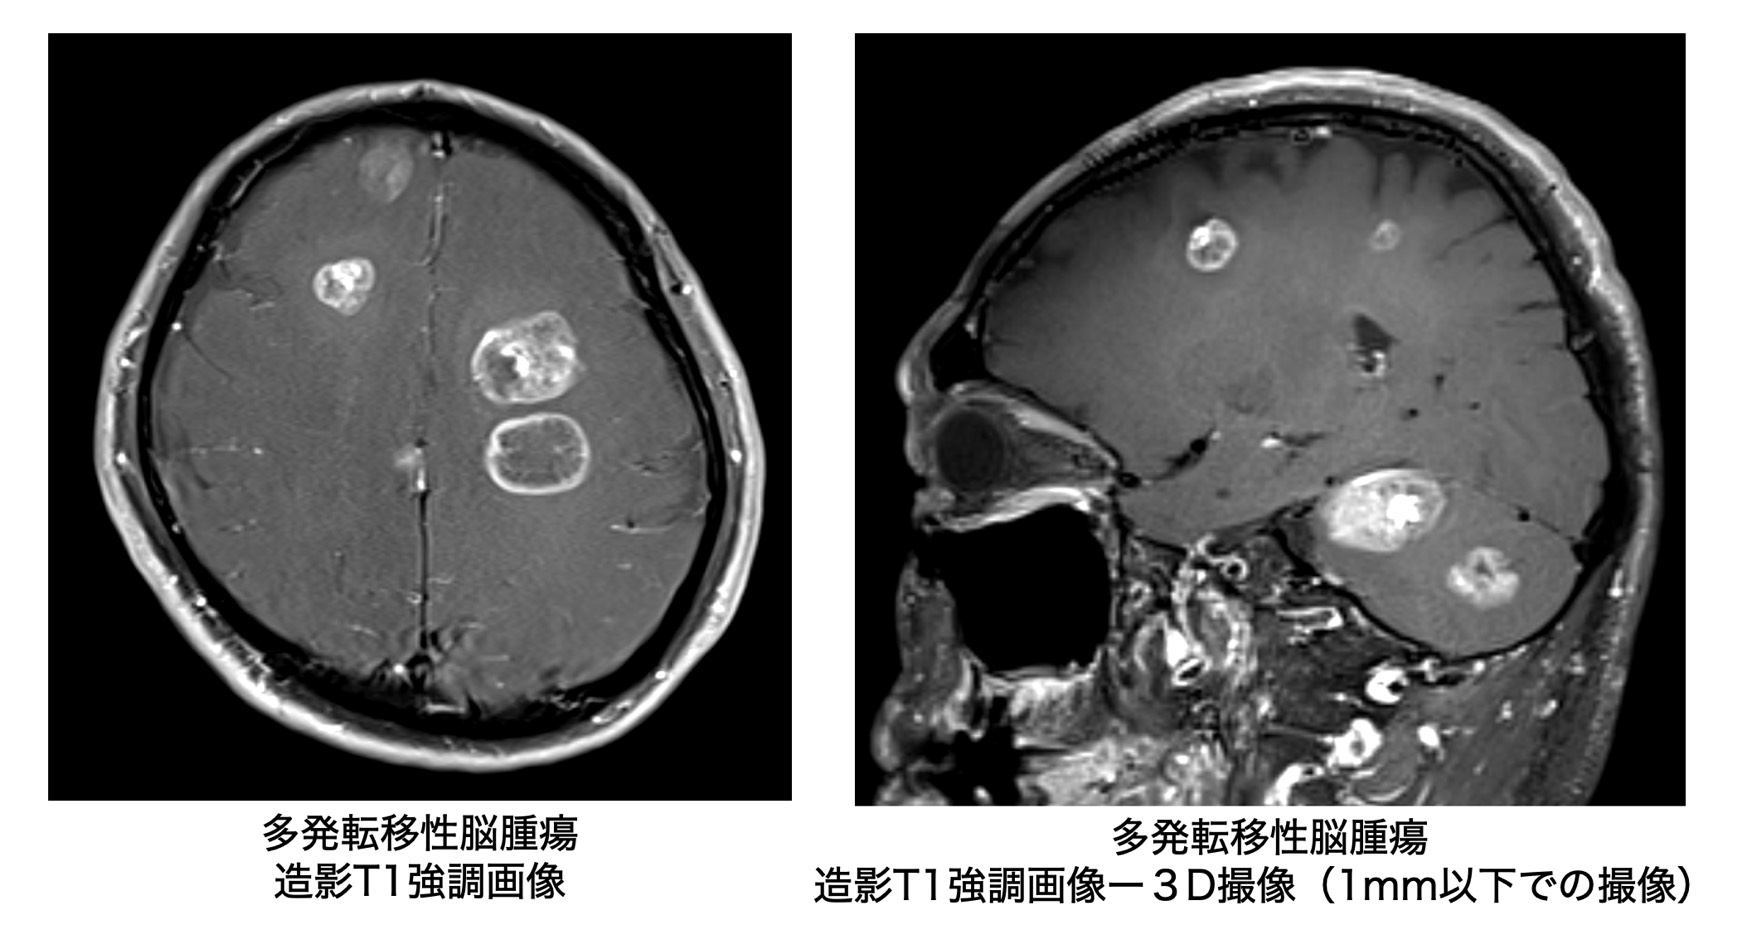

FSLを用いたシェルスクリプト演習:脳3次元T1強調MRIの水平断